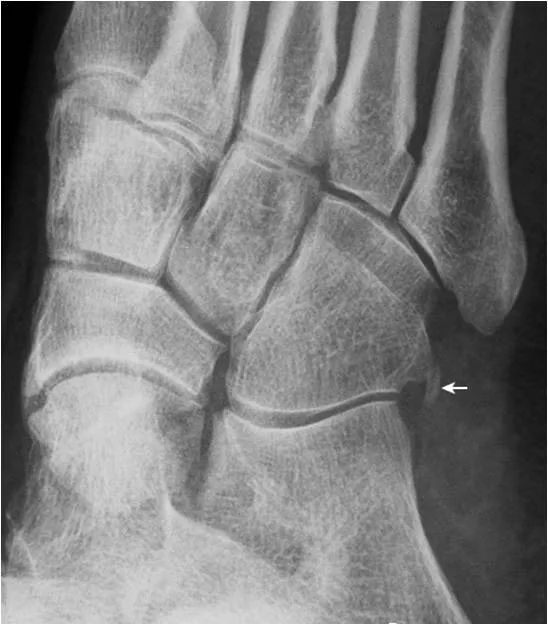

10舟骨下骨:

舟骨下骨是位于舟骨与中间楔骨关节背侧的骨性结节(箭),为一副骨,需与关节面骨赘及撕脱骨折鉴别。另可见腓骨小骨(箭头)。